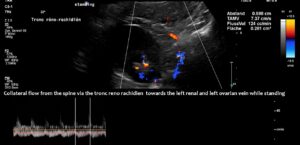

The main driving force was the compression of the left renal vein, as this vein transports most of the blood in the lower body hemisphere. Compression of this vein forces blood to run down the left ovarian vein towards the left internal and common iliac veins. The blood then tries to cross the spine to reach the inferior vena cava. This vessel returns blood to the heart. However, in this patient, the left common iliac vein was also compressed. Consequently, the increased pressure in the left renal vein could only be relieved by creating an additional collateral pathway. This connects the left renal vein with the spinal canal and is called tronc réno-rachidièn .

Large volumes of blood from the left renal vein enter the spinal canal and run along the spinal veins (epidural plexus) towards the skull, entering the intracranial sinuses. They can then leave the skull via the vertebral veins, but mainly via the jugular veins.